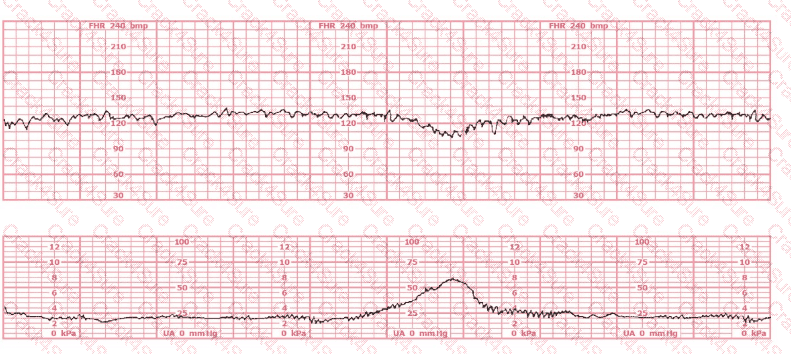

A woman at 38-weeks gestation is admitted to labor and delivery following a fall down the stairs three hours ago. She started feeling contractions in the ambulance. The fetal heart rate tracing shown is on initial evaluation and represents 25 minutes. This tracing is most consistent with a